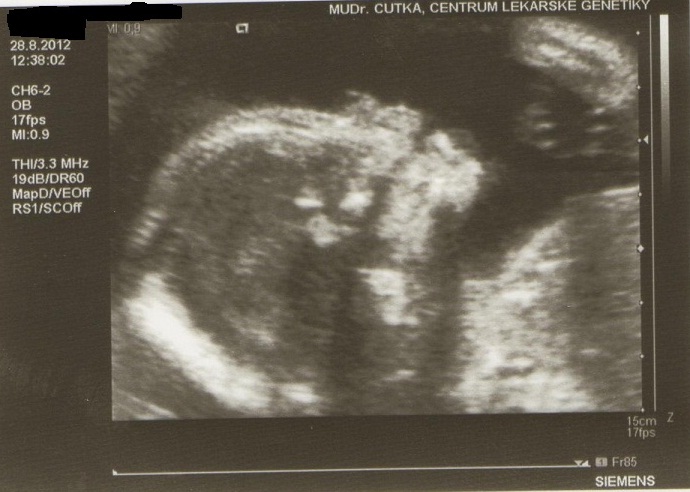

Holky přidávám fotečky naší malinké z minulého týdnu z velkého utz. Dostali jsme tři na dvou je skoro celá a na jedné je záběr na pusinku.